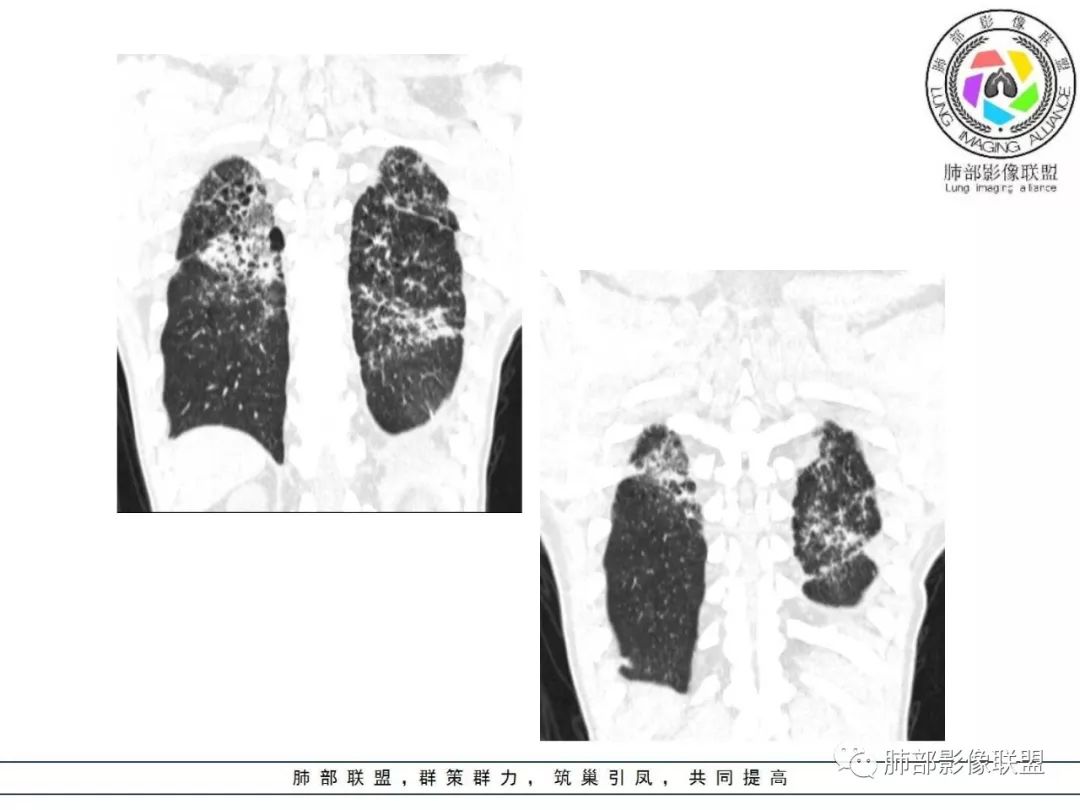

双肺间质性病变,中央间质增厚,胸膜下间质增厚,左侧胸膜肥厚,胸廓变小,肋间隙变窄。

胸部CT:两肺弥漫病灶,磨玻璃影,少许实变,部分累及胸膜,磨玻璃区可见囊?少许胸腔积液,两肺可见结节,支气管血管束增粗,小叶间隔增厚,支气管走形有扭曲扩张,可见纤维化。气肿、大泡。考虑:感染性病变,PCP?查下HIV,CD4,G等。鉴别结核、结缔组织病肺浸润。

胸部CT:两肺弥漫病灶,中央间质分布为主,部分位于胸膜及叶间裂旁,磨玻璃影,斑片影,部分实性结节,肺气囊,支气管血管束增粗,小叶间隔增厚,叶间裂不均匀增厚,支气管走形有扭曲扩张,可见纤维化、气肿、大泡。考虑:LIP加MALT。鉴别PLCH、PCP、结核、结缔组织病肺浸润。

病灶呈片状磨玻璃密度影,呈典型的烟花征。磨玻璃影密度偏高,有网结节样改变,与正常肺实质分界清楚,且常见相对高密度的勾画。

烟花征分为3肿类型:晕征、反晕征及均匀分布。

病变一般沿血管支气管束分布或小叶分布,一般上肺多于下肺(这与常见继发性肺结核分布相若)。

2. 肺气肿背景(小叶中心性肺气肿);双肺多发病灶整体沿血管支气管束及胸膜下分布,以上叶及下叶背段分布为主,有实变及GGO,边界清楚,有树芽,小叶间隔及中央间质增厚,叶间裂见到多发结节,部分支气管不规则牵拉扩张,提示病灶纤维化明显,结合临床病史,考虑病灶为间质性感染,肺门及纵隔内有钙化淋巴结,小叶间隔结节,考虑淋巴道增值性疾病可能,综合常规要怀疑间质性肺结核。